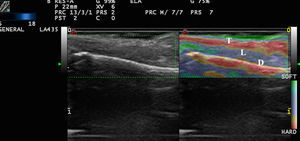

In a study by Bhatia et al.,22 52 non-nodal neck masses were evaluated using real-time qualitative ultrasound elastography. The diagnosis of the lesions was later corroborated by cytology and histology. The lesions were evaluated semiquantitatively on a scale of 0 to 3, where 0 was completely soft and 3 was completely stiff. Lipomas were less stiff than other types of lesions, most of which were cysts, malformations, and neurogenic tumors (Fig. 4). In an extension of the study, SWE was used to assess malignant and benign neck tumors.23 The mean stiffness of the malignant tumors (226.4kPa) was higher than that of the benign lesions (28.3kPa) and the difference was statistically significant. With a cut-off of 174.4kPa, sensitivity of 83.3% and specificity of 97.5% were achieved in the differentiation of benign and malignant lesions. The authors noted that all tumors were correctly diagnosed with conventional ultrasound and that elastography would not have altered the treatment, but they argued that less experienced operators could find the technique helpful in the diagnosis of neck lesions.

Park et al.24 used elastography to differentiate inflamed and unruptured epidermal cysts (Fig. 4, B), the latter being stiffer than the former.